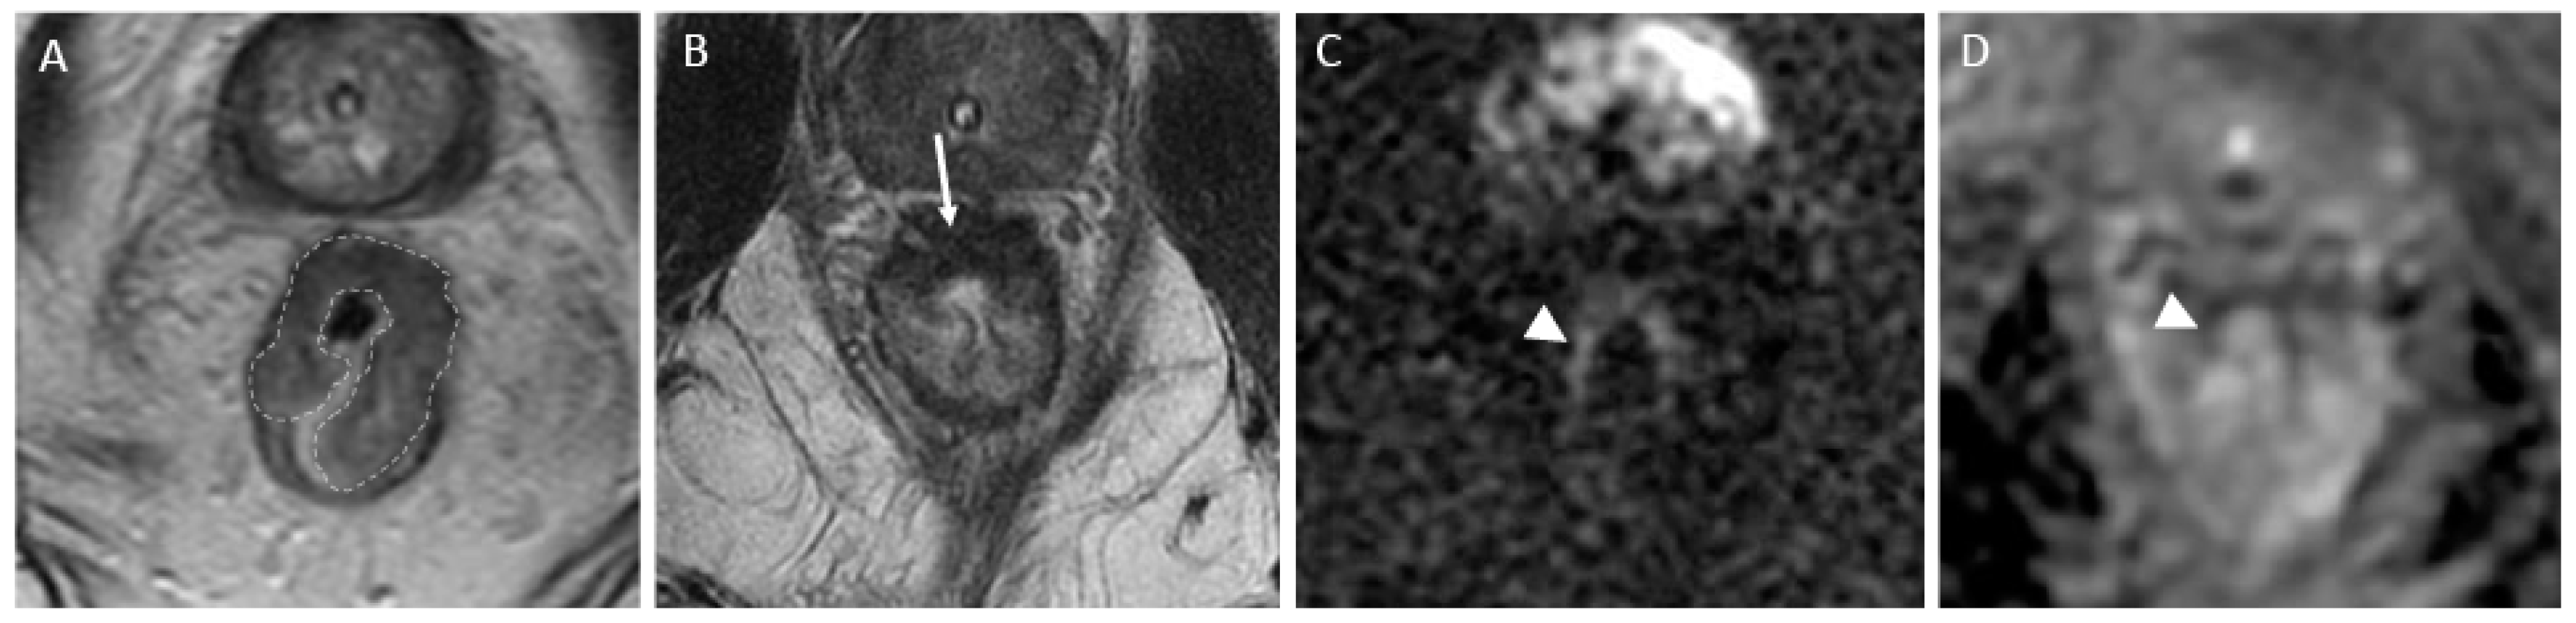

- CR signifies the remarkable disappearance of T2 intermediate signal, indicating a significant reduction in tumor size and suggesting a highly favorable response to treatment. Changes in T2-weighted imaging and DWI pertaining to CR are described below and exemplified in Figure 2:

- T2-weighted imaging—In T2-weighted imaging, CR can be represented as a linear or crescent-shaped scar within the mucosal/ submucosal layers or even the normalization of the rectal wall. It is known that rectal wall normalization can be seen in 5% of cases and is suggestive of CR [64].

- DWI—CR on DWI is characterized by the absence of high signal intensity on high b-value DW images [65,66,67,68]. It is essential to compare DW images at restaging with baseline images and with the normal rectum as references. This can be especially valuable in identifying CR in small, subcircumferential scars [69].

Figure 2.

Complete response after neoadjuvant chemotherapy in a 54-year-old man with low rectal adenocarcinoma. (A) Baseline axial T2-weighted MR image shows a low rectal tumor (dotted line). (B) Axial T2-weighted MR image after the completion of neoadjuvant chemoradiotherapy shows a thick hypointense scar at the site of the treated tumor (arrow). No diffusion restriction was present on diffusion-weighted images (C), and no residual malignancy was identified at endoscopy (D). The patient was offered a watch-and-wait (non-operative management) strategy and has been without evidence of disease for 36 months.